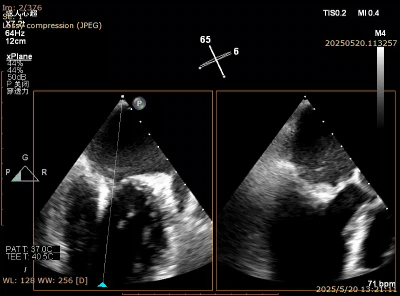

对于交界区病例,传统的做法是先夹合交界区,然后再夹合中央区。但是,对有些挑战病例,靠交界区瓣叶甩动严重,难以充分捕获瓣叶。这时候,可以反常规,先夹合靠中央区甩动不严重的瓣叶,限制了交界区瓣叶的甩动,再夹合交界区的瓣叶。这种情况下,交界区被第一个夹夹合后剩下一个小孔,进去输送系统难度较大,需要术者精细操作,避免将第一个夹子搅拌脱落。另外,该方法夹子几乎是有去无回,一旦进入后左心室后无法再撤出到心房,因此在心房侧就要把夹子和弹道调整到满意的状态,然后小心推送夹子通过小孔进入左心室内(图8-11)。但这种方法往往可以把交界区瓣叶夹合很大量,相对传统方法效果更好。

图8. 上一个病例,Barlow样改变,A3,P2, P3脱垂,靠内交界区甩动更严重

图9. 2.5区植入一枚夹子后,内交接残余脱垂

图10. 从小孔送入第二个夹子

图11. 最后结果满意